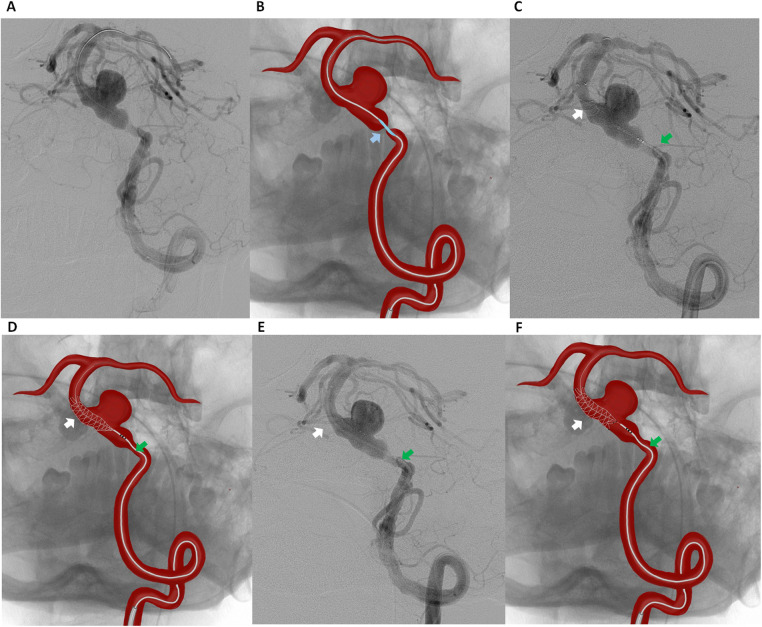

背景:复杂基底动脉动脉瘤的治疗具有挑战性,因为其解剖位置较深,靠近关键穿动脉,并且其频繁的梭状形态和与长段狭窄或动脉粥样硬化改变有关。血管内分流已成为重要的选择;然而,它在大的和梭状的基底动脉动脉瘤中的应用是复杂的,因为装置错位、移动和不完全闭塞的风险。病例介绍:我们报告一例大基底动脉瘤伴严重动脉瘤前狭窄的病例,采用套筒式血流分流术治疗。在支架部署之前进行球囊血管成形术以优化血管直径,然后依次从远端到近端放置重叠的血流分流器。术后血管造影显示设备不稳定,需要在“支架内支架”配置中部署额外的分流器,以改善管壁的放置并防止迁移。这种方法导致持续的动脉瘤血栓形成和长期的血管通畅。结论:本病例说明了处理复杂基底动脉动脉瘤的技术挑战,并强调了辅助支架置入在稳定血流分流器中的作用。考虑到梭状形态、长段动脉受损伤、动脉粥样硬化改变和穿孔丰富的环境,以及需要套筒重建或辅助球囊血管成形术等技术挑战,仔细个性化的血管内策略对于提高手术安全性和实现高风险患者持久的动脉瘤闭塞至关重要。

Case presentation: We report a case of a large basilar artery aneurysm with severe pre-aneurysmal stenosis treated using a telescopic flow-diverter strategy. Balloon angioplasty prior to stent deployment was performed to optimize vessel diameter, followed by the sequential distal-to- proximal placement of overlapping flow diverters. Post-procedural angiography revealed device instability, necessitating the deployment of an additional flow diverter in a "stent-within-a-stent" configuration to improve wall apposition and prevent migration. This approach resulted in sustained aneurysm thrombosis and long-term vessel patency.